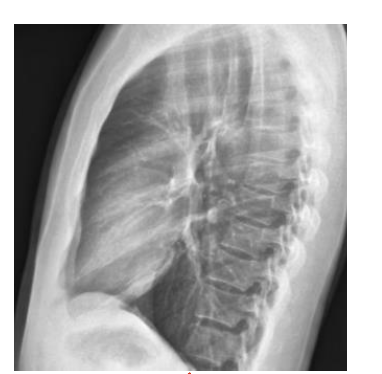

Identify the structure ? View?

Sternum, Lateral View